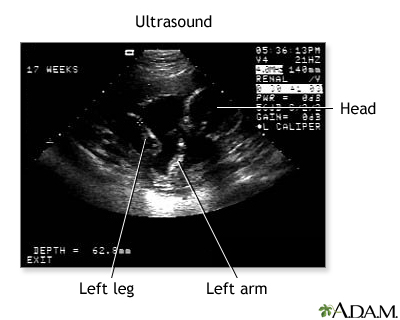

BACK TOTOP Browse A-ZSearchBrowse A-ZABCDEFGHIJKLMNOPQRSTUVWXYZ0-9 E-mail FormEmail ResultsName:Email address:Recipients Name:Recipients address:Message: Print-FriendlyBookmarksbookmarks-menuUltrasound pregnancyPregnancy sonogram; Obstetric ultrasonography; Obstetric sonogram; Ultrasound - pregnancy; IUGR - ultrasound; Intrauterine growth - ultrasound; Polyhydramnios - ultrasound; Oligohydramnios - ultrasound; Placenta previa - ultrasound; Multiple pregnancy - ultrasound; Vaginal bleeding during pregnancy - ultrasound; Fetal monitoring - ultrasoundA pregnancy ultrasound is an imaging test that uses sound waves to create a picture of how a baby is developing in the womb (uterus). It is also used to check the female pelvic organs during pregnancy.No audio descriptionWith audio descriptionRelated video goes here for no-HTML5 browsersRelated video goes here for no-HTML5 browsers How the Test is Performed To have the procedure:You will lie on your back on an exam table. The person performing the test will spread a clear, water-based gel on your belly and pelvis area. A handheld probe will then be moved over the area. The gel helps the probe transmit sound waves. These waves bounce off the body structures, including the developing baby, to create a picture on the ultrasound machine. In some cases, a pregnancy ultrasound may be done by placing the probe into the vagina. This is more likely in early pregnancy. Many women will have the length of their cervix measured by vaginal ultrasonography around 20 to 24 weeks of pregnancy.Placing the probe into the vaginaTransvaginal ultrasound is a test used to look at a woman's uterus, ovaries, tubes, cervix, and pelvic area. Transvaginal means across or through the...ImageRead Article Now Book Mark Article How to Prepare for the Test You will need to have a full bladder to get the best ultrasound image. You may be asked to drink 2 to 3 glasses of liquid an hour before the test. DO NOT urinate before the procedure. How the Test will Feel There may be some discomfort from pressure on the full bladder. The conducting gel may feel slightly cold and wet. You will not feel the ultrasound waves. Why the Test is Performed An ultrasound may be done to determine if there is a problem with the pregnancy, how far along the pregnancy is, or to take measurements and screen for potential problems.Talk to your health care provider to determine the most appropriate scanning schedule for you.A pregnancy ultrasound may be done during the first 12 weeks of pregnancy to:Confirm a normal pregnancy Determine the baby's age Look for problems, such as ectopic pregnancies or the chances for a miscarriage Determine the baby's heart rate Look for multiple pregnancies (such as twins and triplets) Identify problems of the placenta, uterus, cervix, and ovaries Look for findings that might indicate an increased risk for Down syndromeDown syndromeThe nuchal translucency test measures the nuchal fold thickness. This is an area of tissue at the back of an unborn baby's neck. Measuring this thi...ImageRead Article Now Book Mark Article A pregnancy ultrasound may also be done in the second and third trimesters to:Determine the baby's age, growth, position, and sometimes sex. Identify any problems with how the fetus is developing. Look for twins or triplets. Look at the placenta, amniotic fluid, and pelvis.Some centers are now performing a pregnancy ultrasound called a nuchal translucency screening test around 9 to 13 weeks of pregnancy. This test is done to look for signs of Down syndrome or other problems in the developing baby. This test is often combined with blood tests to improve the accuracy of results.Ultrasound may also be performed to guide certain diagnostic procedures in the first and second trimesters to test the placenta and amniotic fluid for certain genetic disorders.How many ultrasounds you will need depends on whether a previous scan or blood test has detected problems that require follow-up testing. Normal Results The developing baby, placenta, amniotic fluid, and surrounding structures appear normal for the gestational age.Note: Normal results may vary slightly. Talk to your provider about the meaning of your specific test results. What Abnormal Results Mean Abnormal ultrasound results may be due to some of the following conditions:Birth defects Ectopic pregnancy Ectopic pregnancyAn ectopic pregnancy is a pregnancy that occurs outside the womb (uterus).ImageRead Article Now Book Mark Article Poor growth of a baby while in the mother's womb Multiple pregnancies Miscarriage Problems with the baby's position in the womb Problems with the placenta, including placenta previa and placental abruption Too little amniotic fluid Too much amniotic fluid (polyhydramnios) PolyhydramniosPolyhydramnios occurs when too much amniotic fluid builds up during pregnancy. It is also called amniotic fluid disorder, or hydramnios.ImageRead Article Now Book Mark Article Tumors of pregnancy, including gestational trophoblastic disease Other problems with the ovaries, uterus, and remaining pelvic structures Risks Current ultrasound techniques appear to be safe. Ultrasound does not involve radiation. Open ReferencesReferencesDugoff L, Wapner RJ. Prenatal diagnosis of congenital disorders. In: Lockwood CJ, Copel JA, Dugoff L, et al, eds. Creasy and Resnik's Maternal-Fetal Medicine: Principles and Practice. 9th ed. Philadelphia, PA: Elsevier; 2023:chap 30.Richards DS. Obstetric ultrasound: imaging, dating, growth, and anomaly. In: Landon MB, Galan HL, Jauniaux ERM, et al, eds. Gabbe's Obstetrics: Normal and Problem Pregnancies. 8th ed. Philadelphia, PA: Elsevier; 2021:chap 9.Wolf RB. Fetal abdominal imaging. In: Lockwood CJ, Copel JA, Dugoff L, et al, eds. Creasy and Resnik's Maternal-Fetal Medicine: Principles and Practice. 9th ed. Philadelphia, PA: Elsevier; 2023:chap 24.AllVideoImagesTogUltrasound in pregnancy - illustration The ultrasound has become a standard procedure used during pregnancy. It can demonstrate fetal growth and can detect increasing numbers of conditions including meningomyelocele, congenital heart disease, kidney abnormalities, hydrocephalus, anencephaly, club feet, and other deformities. Ultrasound does not produce ionizing radiation and is considered a very safe procedure for both the mother and the fetus.Ultrasound in pregnancyillustrationUltrasound, normal fetus - abdomen measurements - illustration This is a normal fetal ultrasound performed at 19 weeks gestation. Many health care providers like to have fetal measurements to verify the size of the fetus and to look for any abnormalities. This ultrasound is of an abdominal measurement. It shows a cross-section of the abdomen, and the measurements are indicated by the cross hairs and dotted lines.Ultrasound, normal fetus - abdomen measurementsillustrationUltrasound, normal fetus - arm and legs - illustration This is a normal fetal ultrasound performed at 17 weeks gestation. This is the type of image pregnant mothers may see on the ultrasound screen, or that the technician may print. It shows the head on the right, and the cross hair pointing to the left ankle. The left leg and arm are visible in the center of the screen.Ultrasound, normal fetus - arm and legsillustrationUltrasound, normal placenta - Braxton Hicks - illustration This is a normal ultrasound performed at 17 weeks gestation. It shows the placenta during a normal (Braxton Hicks) contraction. Throughout the pregnancy, the uterus periodically contracts to facilitate better blood flow through the placenta and the fetus. In this ultrasound, the placenta can be seen as the mound-shaped object in the middle of the screen. At the bottom of the image, the mother's vertebra can be seen as a round object. When the uterus is not contracting, the placenta would appear much flatter.Ultrasound, normal placenta - Braxton HicksillustrationUltrasound, normal fetus - face - illustration This is a normal ultrasound of the fetus performed at 17 weeks gestation. The fetal face can be seen in the middle of the screen. The head is tilted left toward the placenta, which can be seen as a mound in the left of the ultrasound image. Both eyes are visible, and the area of white within the eye is the lens. Other facial features, such as the nose and mouth, are also visible.Ultrasound, normal fetus - faceillustrationUltrasound, normal fetus - femur measurement - illustration This is a normal ultrasound of the fetus performed at 19 weeks gestation. A clear view of the left femur (the large bone of the leg) can be seen in the middle, towards the top of the ultrasound screen.Ultrasound, normal fetus - femur measurementillustrationUltrasound, normal fetus - foot - illustration This is a normal ultrasound of a fetus at 19 weeks gestation. The right foot, including the developing bones, are clearly visible in the middle of the screen.Ultrasound, normal fetus - footillustrationUltrasound, normal fetus - head measurements - illustration This is a normal fetal ultrasound performed at 19 weeks gestation. Many health care providers like to have fetal measurements to verify the size of the fetus and to look for any abnormalities. This ultrasound is of a head measurement, indicated by the cross hairs and dotted lines.Ultrasound, normal fetus - head measurementsillustrationUltrasound, normal fetus - heartbeat - illustration This is a normal fetal ultrasound showing one pattern of the fetal heartbeat. Some ultrasound machines have the ability to focus on different areas of the heart and evaluate the heartbeat. This is useful in the early diagnosis of congenital heart abnormalities.Ultrasound, normal fetus - heartbeatillustrationUltrasound, ventricular septal defect - heartbeat - illustration This is an ultrasound showing a ventricular septal defect pattern of the fetal heartbeat. Some ultrasound machines have the ability to focus on different areas of the heart and evaluate the heartbeat. This is useful in the early diagnosis of congenital heart abnormalities.Ultrasound, ventricular septal defect - heartbeatillustrationUltrasound, normal fetus - arms and legs - illustration This is a normal fetal ultrasound performed at 19 weeks gestation. This is the type of spilt-screen display you might see during an ultrasound, or if the technician prints a copy of the ultrasound for you. This ultrasound shows both the left arm (seen in the left side of the display), and the lower extremities (seen in the right side of the display). The white areas of the arm or legs is developing bone.Ultrasound, normal fetus - arms and legsillustrationUltrasound, normal relaxed placenta - illustration This is a normal fetal ultrasound performed at 19 weeks gestation. This ultrasound shows two interesting features. In the foreground, to the left and middle of the screen, you can see the placenta, following the curve of the uterus. In the background on the right, where the cross hair is pointing, you can see the face with all the facial features visible.Ultrasound, normal relaxed placentaillustrationUltrasound, normal fetus - profile view - illustration This is a normal fetal ultrasound performed at 17 weeks gestation. In the middle of the screen, the profile of the fetus is visible. The outline of the head can be seen in the left middle of the screen with the face down and the body in the fetal position extending to the lower right of the head. The outline of the spine can be seen on the right middle side of the screen.Ultrasound, normal fetus - profile viewillustrationUltrasound, normal fetus - spine and ribs - illustration This is a normal fetal ultrasound performed at 30 weeks gestation. In the middle of the screen, a clear outline of the spine and ribs is visible. The cross hair is between two ribs just above the spine.Ultrasound, normal fetus - spine and ribsillustrationUltrasound, color - normal umbilical cord - illustration This is a normal color Doppler ultrasound of the umbilical cord performed at 30 weeks gestation. The cord is the colored area in the middle of the screen, with the different blood vessels represented by different colors. There are normally three vessels in the cord, two arteries and one vein. The umbilical cord is connected to the placenta, located in the middle left of the image.Ultrasound, color - normal umbilical cordillustrationUltrasound, normal fetus - ventricles of brain - illustration This is a normal fetal ultrasound performed at 17 weeks gestation. The development of the brain and nervous system begins early in fetal development. During an ultrasound, the technician usually looks for the presence of brain ventricles. Ventricles are spaces in the brain that are filled with fluid. In this early ultrasound, the ventricles can be seen as light lines extending through the skull, seen in the upper right side of the image. The cross hair is pointing to the front of the skull, and directly to the right, the lines of the ventricles are visible.Ultrasound, normal fetus - ventricles of brainillustrationPrenatal ultrasound - series - Procedure, part 1Presentation 3D ultrasound - illustration 3D ultrasound provides a three dimensional image of the fetus. Sound waves are sent at different angles by the transducer for the computer to reconstruct the height, width, and depth of the image.3D ultrasoundillustrationUltrasound in pregnancy - illustration The ultrasound has become a standard procedure used during pregnancy. It can demonstrate fetal growth and can detect increasing numbers of conditions including meningomyelocele, congenital heart disease, kidney abnormalities, hydrocephalus, anencephaly, club feet, and other deformities. Ultrasound does not produce ionizing radiation and is considered a very safe procedure for both the mother and the fetus.Ultrasound in pregnancyillustrationUltrasound, normal fetus - abdomen measurements - illustration This is a normal fetal ultrasound performed at 19 weeks gestation. Many health care providers like to have fetal measurements to verify the size of the fetus and to look for any abnormalities. This ultrasound is of an abdominal measurement. It shows a cross-section of the abdomen, and the measurements are indicated by the cross hairs and dotted lines.Ultrasound, normal fetus - abdomen measurementsillustrationUltrasound, normal fetus - arm and legs - illustration This is a normal fetal ultrasound performed at 17 weeks gestation. This is the type of image pregnant mothers may see on the ultrasound screen, or that the technician may print. It shows the head on the right, and the cross hair pointing to the left ankle. The left leg and arm are visible in the center of the screen.Ultrasound, normal fetus - arm and legsillustrationUltrasound, normal placenta - Braxton Hicks - illustration This is a normal ultrasound performed at 17 weeks gestation. It shows the placenta during a normal (Braxton Hicks) contraction. Throughout the pregnancy, the uterus periodically contracts to facilitate better blood flow through the placenta and the fetus. In this ultrasound, the placenta can be seen as the mound-shaped object in the middle of the screen. At the bottom of the image, the mother's vertebra can be seen as a round object. When the uterus is not contracting, the placenta would appear much flatter.Ultrasound, normal placenta - Braxton HicksillustrationUltrasound, normal fetus - face - illustration This is a normal ultrasound of the fetus performed at 17 weeks gestation. The fetal face can be seen in the middle of the screen. The head is tilted left toward the placenta, which can be seen as a mound in the left of the ultrasound image. Both eyes are visible, and the area of white within the eye is the lens. Other facial features, such as the nose and mouth, are also visible.Ultrasound, normal fetus - faceillustrationUltrasound, normal fetus - femur measurement - illustration This is a normal ultrasound of the fetus performed at 19 weeks gestation. A clear view of the left femur (the large bone of the leg) can be seen in the middle, towards the top of the ultrasound screen.Ultrasound, normal fetus - femur measurementillustrationUltrasound, normal fetus - foot - illustration This is a normal ultrasound of a fetus at 19 weeks gestation. The right foot, including the developing bones, are clearly visible in the middle of the screen.Ultrasound, normal fetus - footillustrationUltrasound, normal fetus - head measurements - illustration This is a normal fetal ultrasound performed at 19 weeks gestation. Many health care providers like to have fetal measurements to verify the size of the fetus and to look for any abnormalities. This ultrasound is of a head measurement, indicated by the cross hairs and dotted lines.Ultrasound, normal fetus - head measurementsillustrationUltrasound, normal fetus - heartbeat - illustration This is a normal fetal ultrasound showing one pattern of the fetal heartbeat. Some ultrasound machines have the ability to focus on different areas of the heart and evaluate the heartbeat. This is useful in the early diagnosis of congenital heart abnormalities.Ultrasound, normal fetus - heartbeatillustrationUltrasound, ventricular septal defect - heartbeat - illustration This is an ultrasound showing a ventricular septal defect pattern of the fetal heartbeat. Some ultrasound machines have the ability to focus on different areas of the heart and evaluate the heartbeat. This is useful in the early diagnosis of congenital heart abnormalities.Ultrasound, ventricular septal defect - heartbeatillustrationUltrasound, normal fetus - arms and legs - illustration This is a normal fetal ultrasound performed at 19 weeks gestation. This is the type of spilt-screen display you might see during an ultrasound, or if the technician prints a copy of the ultrasound for you. This ultrasound shows both the left arm (seen in the left side of the display), and the lower extremities (seen in the right side of the display). The white areas of the arm or legs is developing bone.Ultrasound, normal fetus - arms and legsillustrationUltrasound, normal relaxed placenta - illustration This is a normal fetal ultrasound performed at 19 weeks gestation. This ultrasound shows two interesting features. In the foreground, to the left and middle of the screen, you can see the placenta, following the curve of the uterus. In the background on the right, where the cross hair is pointing, you can see the face with all the facial features visible.Ultrasound, normal relaxed placentaillustrationUltrasound, normal fetus - profile view - illustration This is a normal fetal ultrasound performed at 17 weeks gestation. In the middle of the screen, the profile of the fetus is visible. The outline of the head can be seen in the left middle of the screen with the face down and the body in the fetal position extending to the lower right of the head. The outline of the spine can be seen on the right middle side of the screen.Ultrasound, normal fetus - profile viewillustrationUltrasound, normal fetus - spine and ribs - illustration This is a normal fetal ultrasound performed at 30 weeks gestation. In the middle of the screen, a clear outline of the spine and ribs is visible. The cross hair is between two ribs just above the spine.Ultrasound, normal fetus - spine and ribsillustrationUltrasound, color - normal umbilical cord - illustration This is a normal color Doppler ultrasound of the umbilical cord performed at 30 weeks gestation. The cord is the colored area in the middle of the screen, with the different blood vessels represented by different colors. There are normally three vessels in the cord, two arteries and one vein. The umbilical cord is connected to the placenta, located in the middle left of the image.Ultrasound, color - normal umbilical cordillustrationUltrasound, normal fetus - ventricles of brain - illustration This is a normal fetal ultrasound performed at 17 weeks gestation. The development of the brain and nervous system begins early in fetal development. During an ultrasound, the technician usually looks for the presence of brain ventricles. Ventricles are spaces in the brain that are filled with fluid. In this early ultrasound, the ventricles can be seen as light lines extending through the skull, seen in the upper right side of the image. The cross hair is pointing to the front of the skull, and directly to the right, the lines of the ventricles are visible.Ultrasound, normal fetus - ventricles of brainillustration Prenatal ultrasound - series - Procedure, part 1Presentation 3D ultrasound - illustration 3D ultrasound provides a three dimensional image of the fetus. Sound waves are sent at different angles by the transducer for the computer to reconstruct the height, width, and depth of the image.3D ultrasoundillustrationSelf Care Vaginal bleeding in early pregnancyPrenatal care in your first trimesterPrenatal care in your second trimesterPreterm laborWhen your baby is stillborn Tests for Ultrasound pregnancy Ultrasound pregnancyTransvaginal ultrasoundUltrasoundPelvic ultrasound - abdominalRelated Information Ectopic pregnancy(Condition)Polyhydramnios(Symptoms)Intrauterine growth restriction(Condition) Review Date: 3/31/2024 Reviewed By: LaQuita Martinez, MD, Department of Obstetrics and Gynecology, Emory Johns Creek Hospital, Alpharetta, GA. Also reviewed by David C. Dugdale, MD, Medical Director, Brenda Conaway, Editorial Director, and the A.D.A.M. Editorial team. The information provided herein should not be used during any medical emergency or for the diagnosis or treatment of any medical condition. A licensed medical professional should be consulted for diagnosis and treatment of any and all medical conditions. Links to other sites are provided for information only -- they do not constitute endorsements of those other sites. No warranty of any kind, either expressed or implied, is made as to the accuracy, reliability, timeliness, or correctness of any translations made by a third-party service of the information provided herein into any other language. © 1997- A.D.A.M., a business unit of Ebix, Inc. Any duplication or distribution of the information contained herein is strictly prohibited. © 1997- All rights reserved. A.D.A.M. content is best viewed in IE9 or above, Firefox and Google Chrome browser.Content is best viewed in IE9 or above, Firefox and Google Chrome browser.